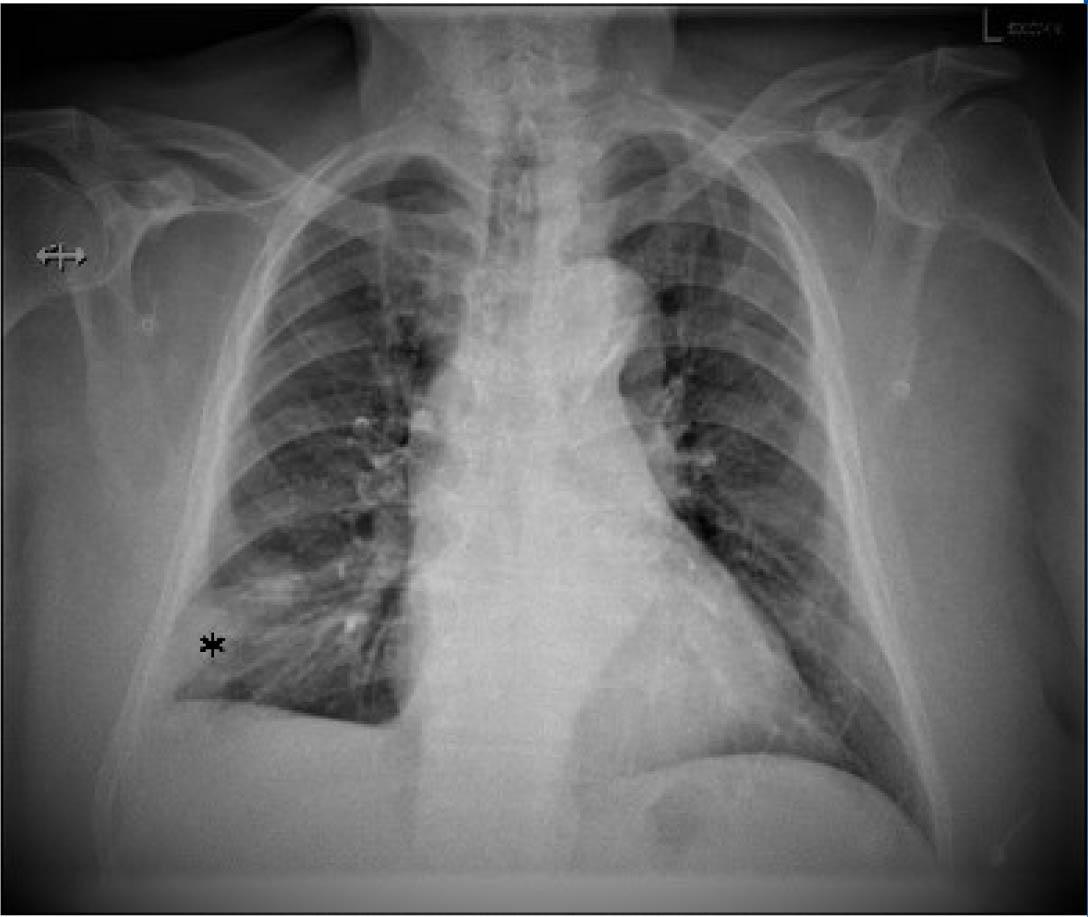

Chest x-ray that shows right lower lobe condensation opacity, without aerial bronchogram suggestive of pulmonary infarct.